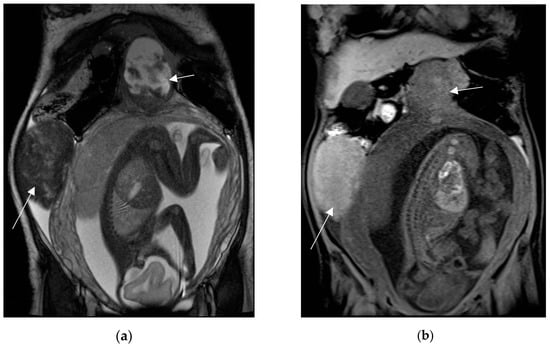

Figure 9.

Left adnexal torsion in 28-year-old patient at 35 weeks of gestation. Axial (a) and coronal (b) T2-weighted images show left cystic formation of about 8 cm (arrow) that has undergone torsion, compressed between the gravid uterus and the abdominal wall.